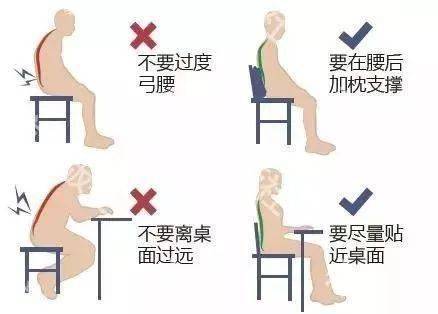

關(guān)于腰椎間盤突出  腰椎間盤突出癥是纖維環(huán)破裂后髓核突出壓迫神經(jīng)根造成以腰腿痛為主要表現(xiàn)的疾病。腰椎間盤退行性改變或外傷所致纖維環(huán)破裂,髓核從破裂處脫出,壓迫腰椎神經(jīng),從而出現(xiàn)腰腿放射性疼痛。  病因: 一、退行性變: 目前認(rèn)為,其基本病因是腰椎間盤的退行性變。退行性變是一切生物生、長、衰、亡的客觀規(guī)律,由于腰椎所承擔(dān)的特殊的生理功能,腰椎間盤的退行性變比 其他組織器官要早,而且進(jìn)展相對要快。這個過程是一個長期,復(fù)雜的過程。所謂腰椎間盤退行性改變:即由于椎間盤受體重的壓迫,加上腰部又經(jīng)常進(jìn)行彎曲、后伸等活動,易造成椎間盤的擠壓和磨損,尤其是下腰部的椎間盤,從而產(chǎn)生退行性改變。腰椎間盤退行性改變是本病發(fā)生的基礎(chǔ)。 二、其他因素: 1、外力作用:在日常生活和工作中,部分人往往存在長期腰部用力不當(dāng)、過度用力姿勢或體位的不正確等情況。例如長期從事彎腰工作的煤礦工人和建筑工人需經(jīng)常彎腰提舉重物。這些長期反復(fù)的外力造成的損傷日積月累地作用于椎間盤,加重了退變的程度。 2、椎間盤自身解剖因素的弱點: (1) 椎間盤在成人之后逐漸缺乏血液循環(huán),修復(fù)能力也較差,特別是在退變產(chǎn)生后,修復(fù)能力更加微弱。 (2) 椎間盤后外側(cè)的纖維環(huán)較為薄弱,而后縱韌帶在腰5、骶1平面時寬度顯著減少,對纖維環(huán)的加強(qiáng)作用明顯減弱。 (3) 腰骶段先天異常:腰骶段畸形可使發(fā)病率增高,這些異常造成椎間隙寬度不等,并常造成關(guān)節(jié)突出,關(guān)節(jié)受到更多的旋轉(zhuǎn)勞損,使纖維環(huán)受到的壓力不一,加速退變。 3、種族、遺傳因素:有色人種發(fā)病率較低,例如印第安人和非洲黑人等發(fā)病率較其他民族明顯要低。  2 病理 腰椎間盤突出癥的病理變化過程大致可分為三個階段: 1、突出前期:髓核因退變和損傷可變成碎塊狀物,或呈瘢痕樣結(jié)締組織,變性的纖維環(huán)可因反復(fù)損傷而變薄變軟或產(chǎn)生裂隙。此期病人可有腰部不適或疼痛,但無放射性下肢痛。也有的人原無病變,可因一次大的暴力引起髓核突出。 2、突出期:外傷或正常的活動使椎間盤壓力增加時,髓核從纖維環(huán)薄弱處或破裂處突出。突出物刺激或壓迫神經(jīng)根即發(fā)生放射性下肢痛,或壓迫馬尾神經(jīng)發(fā)生大小便功能障礙。在老 年患者,可因椎間盤退變,整個纖維環(huán)變得軟弱松弛,椎間盤可呈彌漫性向周圍膨出。 3、突出晚期:腰椎間盤突出后,病程較長者,椎間盤本身和其他鄰近結(jié)構(gòu)均可發(fā)生各種繼發(fā)性病理改變。 3 誘發(fā)因素 腰椎間盤突出癥的基本因素是椎間盤退變,但某些誘發(fā)因素可致使椎間隙壓力增高,引起髓核突出。此種誘發(fā)因素常與以下因素有關(guān): 1. 年齡因素:腰椎間盤突出癥的好發(fā)年齡在30-50歲,平均手術(shù)年齡在40歲,因此退變可能是其重要因素。 2. 身高與性別:有人認(rèn)為身材過高也會易發(fā)腰突癥,而男性發(fā)病率是女性的5倍。 3. 增加腹壓:臨床上有約1/3的病人在發(fā)病前有明確的增加腹壓的因素,如劇烈的咳嗽、噴嚏、屏氣、用力排便等。使腹壓增高,破壞了椎節(jié)與椎管之間的平衡狀態(tài)。 4. 不良體位:人在完成各種工作時,需要不斷更換各種體位以緩解腰部壓力,如長期處于某一體位不變,即可導(dǎo)致局部的累積性損傷。特別是長期處于不良姿勢更容易誘發(fā)本病。 5. 職業(yè)因素:重體力勞動者發(fā)病率最高,白領(lǐng)勞動者最低。汽車駕駛員由于長期處于顛簸和振動狀態(tài),椎間盤承受的壓力大且反復(fù)變化,也易誘發(fā)椎間盤突出。 6. 受寒受濕:寒冷或潮濕可引起小血管收縮、肌肉痙攣,使椎間盤的壓力增加,可能造成退變的椎間盤破裂。     癥狀: 腰椎間盤突出癥患者最多見的癥狀為疼痛,可表現(xiàn)為腰背痛、坐骨神經(jīng)痛,典型的坐骨神經(jīng)痛表現(xiàn)為由臀部、大腿后側(cè)、小腿外側(cè)至跟部或足背的放射痛。據(jù)臨床統(tǒng)計,約95%的腰突癥患者有不同程度的腰痛,80%的患者有下肢痛。特別是腰痛,不僅是腰椎間盤突出最常見的癥狀,也是最早出現(xiàn)的癥狀之一。    檢查: 1、X線:腰椎間盤所包括的髓核、纖維環(huán)和軟骨板密度均較低,在X線下并不顯影,因此臨床上腰突癥患者的腰椎X線平片可僅有一些非特異性的變化,甚至無異常變化。因此單純腰椎平片并不能作為有無腰椎間盤突出癥的直接依據(jù),但X線能發(fā)現(xiàn)腰椎的退行性改變和結(jié)構(gòu)異常,對提示椎間盤的退變有重要意義,并且能排除其他的一些腰椎疾患,如腰椎結(jié)核、腫瘤和腰椎滑脫等。典型的腰椎間盤突出癥患者通過病史、體征和X線平片即能作出初步的診斷。 2、CT檢查:腰椎的CT可以清楚地顯示椎間盤突出的部位、大小、形態(tài)和神經(jīng)根、硬脊膜受壓的情況,同時還可顯示黃韌帶肥厚、小關(guān)節(jié)增生、椎管和側(cè)隱窩狹窄等情況。對腰椎間盤突出癥診斷的準(zhǔn)確率達(dá)到80%-92%。 3、核磁共振(MRI):核磁共振沒有輻射,可以多方位成像(橫斷面、冠狀面、矢狀面和斜面),對解剖細(xì)節(jié)顯示較好,對組織結(jié)構(gòu)的細(xì)微病理變化更敏感(如骨髓的浸潤),可以排除神經(jīng)和脊柱腫瘤等。對于一些落到椎管的髓核組織也不會遺漏。 4、脊髓造影:脊髓造影利用椎管內(nèi)蛛網(wǎng)膜下腔的空隙,注入造影劑后在X線下攝片,顯示椎管內(nèi)部結(jié)構(gòu)。目前常用水溶性造影劑,能較清晰地顯示硬膜腔、馬尾神經(jīng)和神經(jīng)根鞘,對腰椎間盤突出癥的診斷可達(dá)90%左右,主要X線表現(xiàn)為硬膜囊壓迫征象和神經(jīng)根鞘壓迫征象。但由于CT和MRI在臨床的廣泛應(yīng)用,無創(chuàng)傷且診斷率更高,脊髓造影在臨床上的應(yīng)用已經(jīng)大大減少,而且由于它副作用較大,甚至可能造成截癱等嚴(yán)重情況,目前主張慎重選用。 5、肌電圖:肌電圖是對周圍神經(jīng)與肌肉的電生理檢查方法,可用于觀察并記錄肌肉在靜止、主動收縮和支配其的周圍神經(jīng)受刺激時的電活動,同時也可用來測量周圍神經(jīng)的傳導(dǎo)速度。在腰椎間盤突出癥上,肌電圖主要通過檢查雙下肢肌肉的興奮性來反映相應(yīng)神經(jīng)根的狀態(tài),并根據(jù)異常電活動的分布范圍來判斷椎間盤突出和神經(jīng)根受壓的節(jié)段。在脊神經(jīng)根和馬尾神經(jīng)受壓的病人,肌電圖陽性率可達(dá)80%-90%,但與CT和MRI相比并不是首選的檢查手段,可用于輔助診斷和判斷神經(jīng)根的受壓情況,同時也可以用來作為判斷治療后神經(jīng)根恢復(fù)情況的指標(biāo)之一。    預(yù)防: 腰椎間盤突出癥是在退行性變基礎(chǔ)上積累傷所致,積累傷又會加重椎間盤的退變,因此預(yù)防的重點在于減少積累傷。 日常注意事項: 1.平時要有良好的坐姿,睡眠時的床不宜太軟。 2.長期伏案工作者需要注意桌、椅高度,定期改變姿勢。 3.職業(yè)工作中需要常彎腰動作者,應(yīng)定時伸腰、挺胸活動,并使用寬的腰帶。 4.應(yīng)加強(qiáng)腰背肌訓(xùn)練,增加脊柱的內(nèi)在穩(wěn)定性,長期使用腰圍者,尤其需要注意腰背肌鍛煉,以防止失用性肌肉萎縮帶來不良后果。 5.如需彎腰取物,最好采用屈髖、屈膝下蹲方式,減少對腰椎間盤后方的壓力。    治療: (一)中醫(yī)外敷療法: 腰椎間盤突出可以外貼 腰突正骨膏,其有效成分可透入皮膚產(chǎn)生活血,止痛,化淤,通經(jīng)走絡(luò),開竅透骨,祛風(fēng)散寒等效果,并通過藥物的歸經(jīng)作用而調(diào)理機(jī)體陰陽平衡,滲透于表皮,刺激神經(jīng)末梢,促進(jìn)局部血液微循環(huán),扶正固本、改善體質(zhì),從根本上、全方位針對腰椎疾病病機(jī)特點而發(fā)揮療效,改善病變周圍組織營養(yǎng),起到修復(fù)骨病組織的作用,最終達(dá)到治療目的。 (二)自我治療: 1.腹肌鍛煉: 也就是仰臥起坐。每次做十個,每天三次。(可根據(jù)患者的體質(zhì)來定,不可逞強(qiáng))。 2.交叉扭腰: 兩腳分開與肩寬,腳尖向內(nèi)兩臂伸直,一手在體側(cè),一 手舉過頭頂。如果右手在上,先向左側(cè)后方擺。左側(cè)相反。于此同時腰部也隨之扭動,左右各100次。 3.抱膝觸胸: 處于仰臥位,雙膝屈曲,手抱住膝部,使盡量靠近胸部,然后放下,一上一下為一個動作,可持續(xù)30個。 4.腰背肌鍛煉: 處于平臥,雙膝彎曲放在床上,然后用力將臀部抬起,離開床面10厘米。這時您會感覺到腰背部在用力,堅持5秒鐘,反復(fù)10下。  (三)非手術(shù)治療: 非手術(shù)療法是治療腰椎間盤突出癥的基本療法,約80%以上的患者經(jīng)保守治療均可得到緩解和痊愈。其主要療法有: 1.日常家庭治療:早期腰椎間盤突出癥,癥狀輕微,不需要做特殊的治療。第一,注意臥床休息,避免腰椎受外力壓迫,第二,應(yīng)用其他方法積極鍛煉腰部肌肉力量。 2.牽引治療; 3.推拿按摩治療; 4.物理治療; 5.消炎鎮(zhèn)痛藥物; 6.減輕神經(jīng)根水腫藥物。 (四)推拿治療: 1.解除腰臀部肌肉痙攣 2.拉寬椎間隙,降低盤間壓力 3.增加椎間盤外壓力 4.調(diào)整后關(guān)節(jié),松解粘連 5.促使受損傷的神經(jīng)根恢復(fù)功能 (五)微創(chuàng)治療: 微創(chuàng)治療方法的目的是消除腰椎間盤突出的髓核以解除對神經(jīng)的壓迫。微創(chuàng)治療技術(shù)采用可視設(shè)備,創(chuàng)口不足一厘米有些甚至不足一毫米。消融或摘除髓核,從根本上解除致病因素,因而能夠取得很好的效果。 (六)手術(shù)治療: 腰椎間盤突出癥的手術(shù)原則是嚴(yán)格無菌操作,盡量保留不必去除的骨結(jié)構(gòu)和軟組織結(jié)構(gòu),以最小的創(chuàng)傷達(dá)到足夠的顯露,仔細(xì)徹底地去除病變組織,達(dá)到治療目的。   綠柏相關(guān)產(chǎn)品:  懸吊訓(xùn)練療法是康復(fù)醫(yī)學(xué)中以持久改善肌肉骨骼疾病為目的的,應(yīng)用主動治療和訓(xùn)練的一個總的概念整合,是一種運(yùn)動感覺的綜合訓(xùn)練系統(tǒng),包括診斷與治療兩大系統(tǒng)。 產(chǎn)品特點: 1.電腦軟件管理系統(tǒng),涵蓋患者信息管理、評估、訓(xùn)練、量表、報告、視頻教學(xué)六大模塊,輕松實現(xiàn)評估與訓(xùn)練一體化管理; 2.多點多軸設(shè)計,滿足不同治療方案設(shè)計; 3.懸吊工作站及各個懸吊點,均能實現(xiàn)任意位置移動,一鍵解鎖,省時省力; 4.實時力反饋,精準(zhǔn)量化弱鏈測試及懸吊治療全過程,給治療師及患者最直觀的效果呈現(xiàn); 5.智能神經(jīng)肌肉促通裝置,可根據(jù)評估結(jié)果設(shè)置治療模式、頻率、時間等相關(guān)參數(shù),讓懸吊康復(fù)更加高效有針對性; 6.外觀高端大氣,結(jié)構(gòu)穩(wěn)固,給患者安全保障,增加治療信心。  |